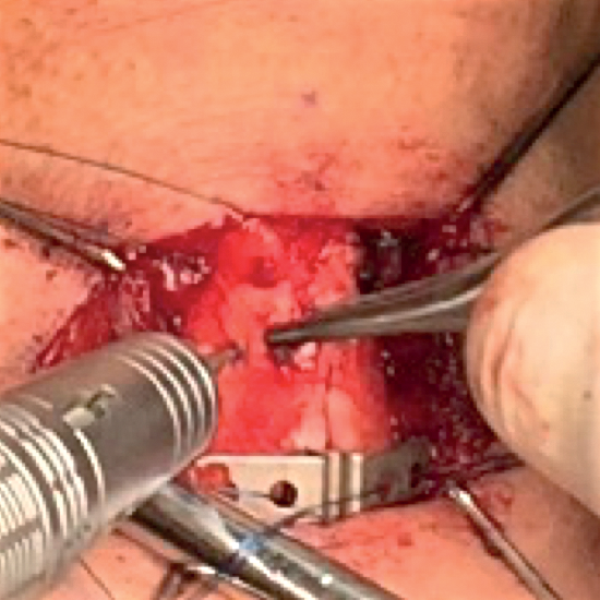

Inserting the titanium bridge

The superior and inferior bridges are inserted in no particular order. The bridge is grasped with a small non-tooth forcep from its holes and gently slides in (Figure 16). The edge of the bridge should lie flush with the edge of the thyroid laminae. There may be some resistance from the perichondrium or a thick cartilage when inserting the bridge. The perichondrium can be further elevated by sharp dissection by another 1mm in the area if the resistance is felt.

Figure 16: Inserting the titanium bridge.